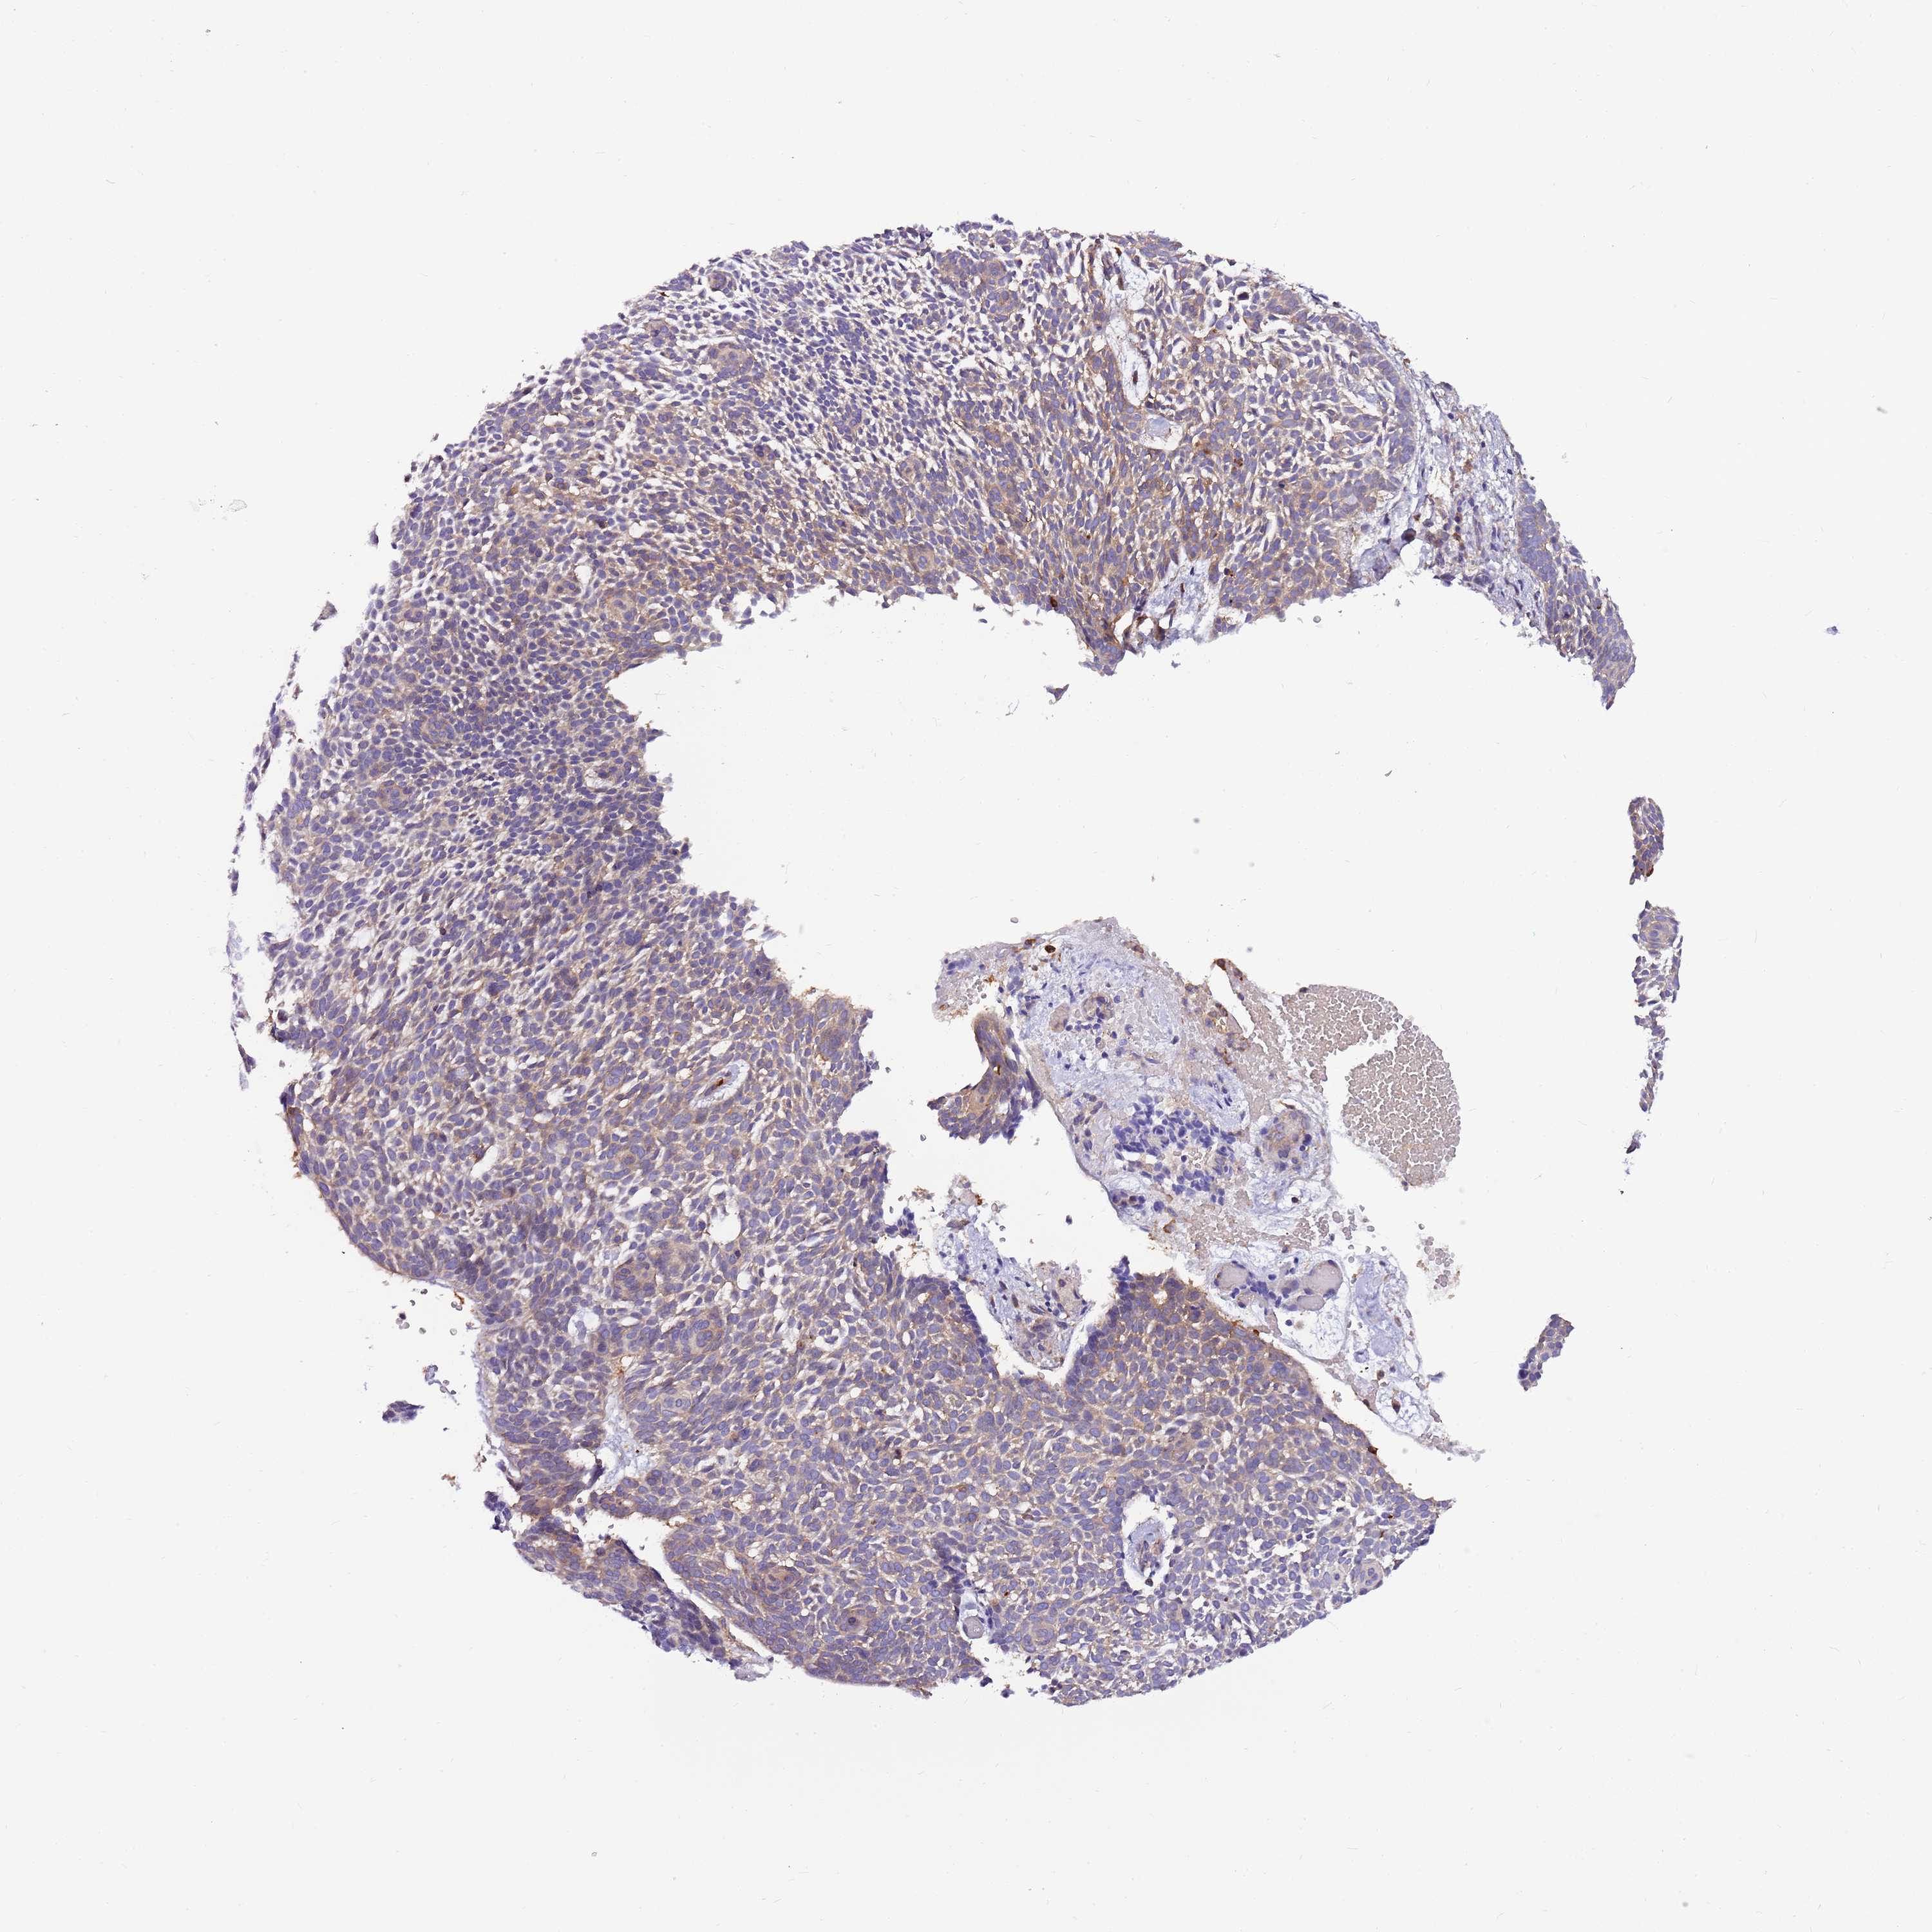

SKIN CANCER - Protein expressioni

A mouse-over function shows sample information and annotation data. Click on an image to view it in a full screen mode. Samples can be filtered based on level of antibody staining by selecting one or several of the following categories: high, medium, low and not detected. The assay and annotation is described here.

Each image is clickable and will lead to virtual microscopy that enables deeper exploration of all samples and also displays staining intensity scores, fraction scores and subcellular localization as well as patient and tissue information for each sample.

Antibody HPA043391

High

Intensity

Quantity

Location

Squamous cell carcinoma, NOS